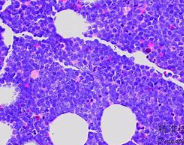

B淋巴细胞B淋巴细胞

B淋巴细胞,也称为B细胞,是一种免疫系统中的重要细胞类型。作为脊椎动物免疫系统的一部分,B淋巴细胞在机体抵御病原体、产生抗体以及调节免疫应答等方面起着关键作用。

B淋巴细胞是一类由骨髓中的造血干细胞发育而来的淋巴细胞。它们主要存在于淋巴组织(如脾脏、淋巴结)和黏膜组织(如肠道和呼吸道)。B淋巴细胞具有特殊的受体,称为B细胞受体(BCR),它能够识别并结合病原体表面的抗原。